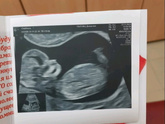

Прошла второй скрининг и расстроилась

Приклеплю фото. Узист смотрел меня минут 40, Крутил то на левый то на правый бок, смотрел кровотоки. Итого плохой кровоток в пуповине. Развитие ребёнка … Читать далее